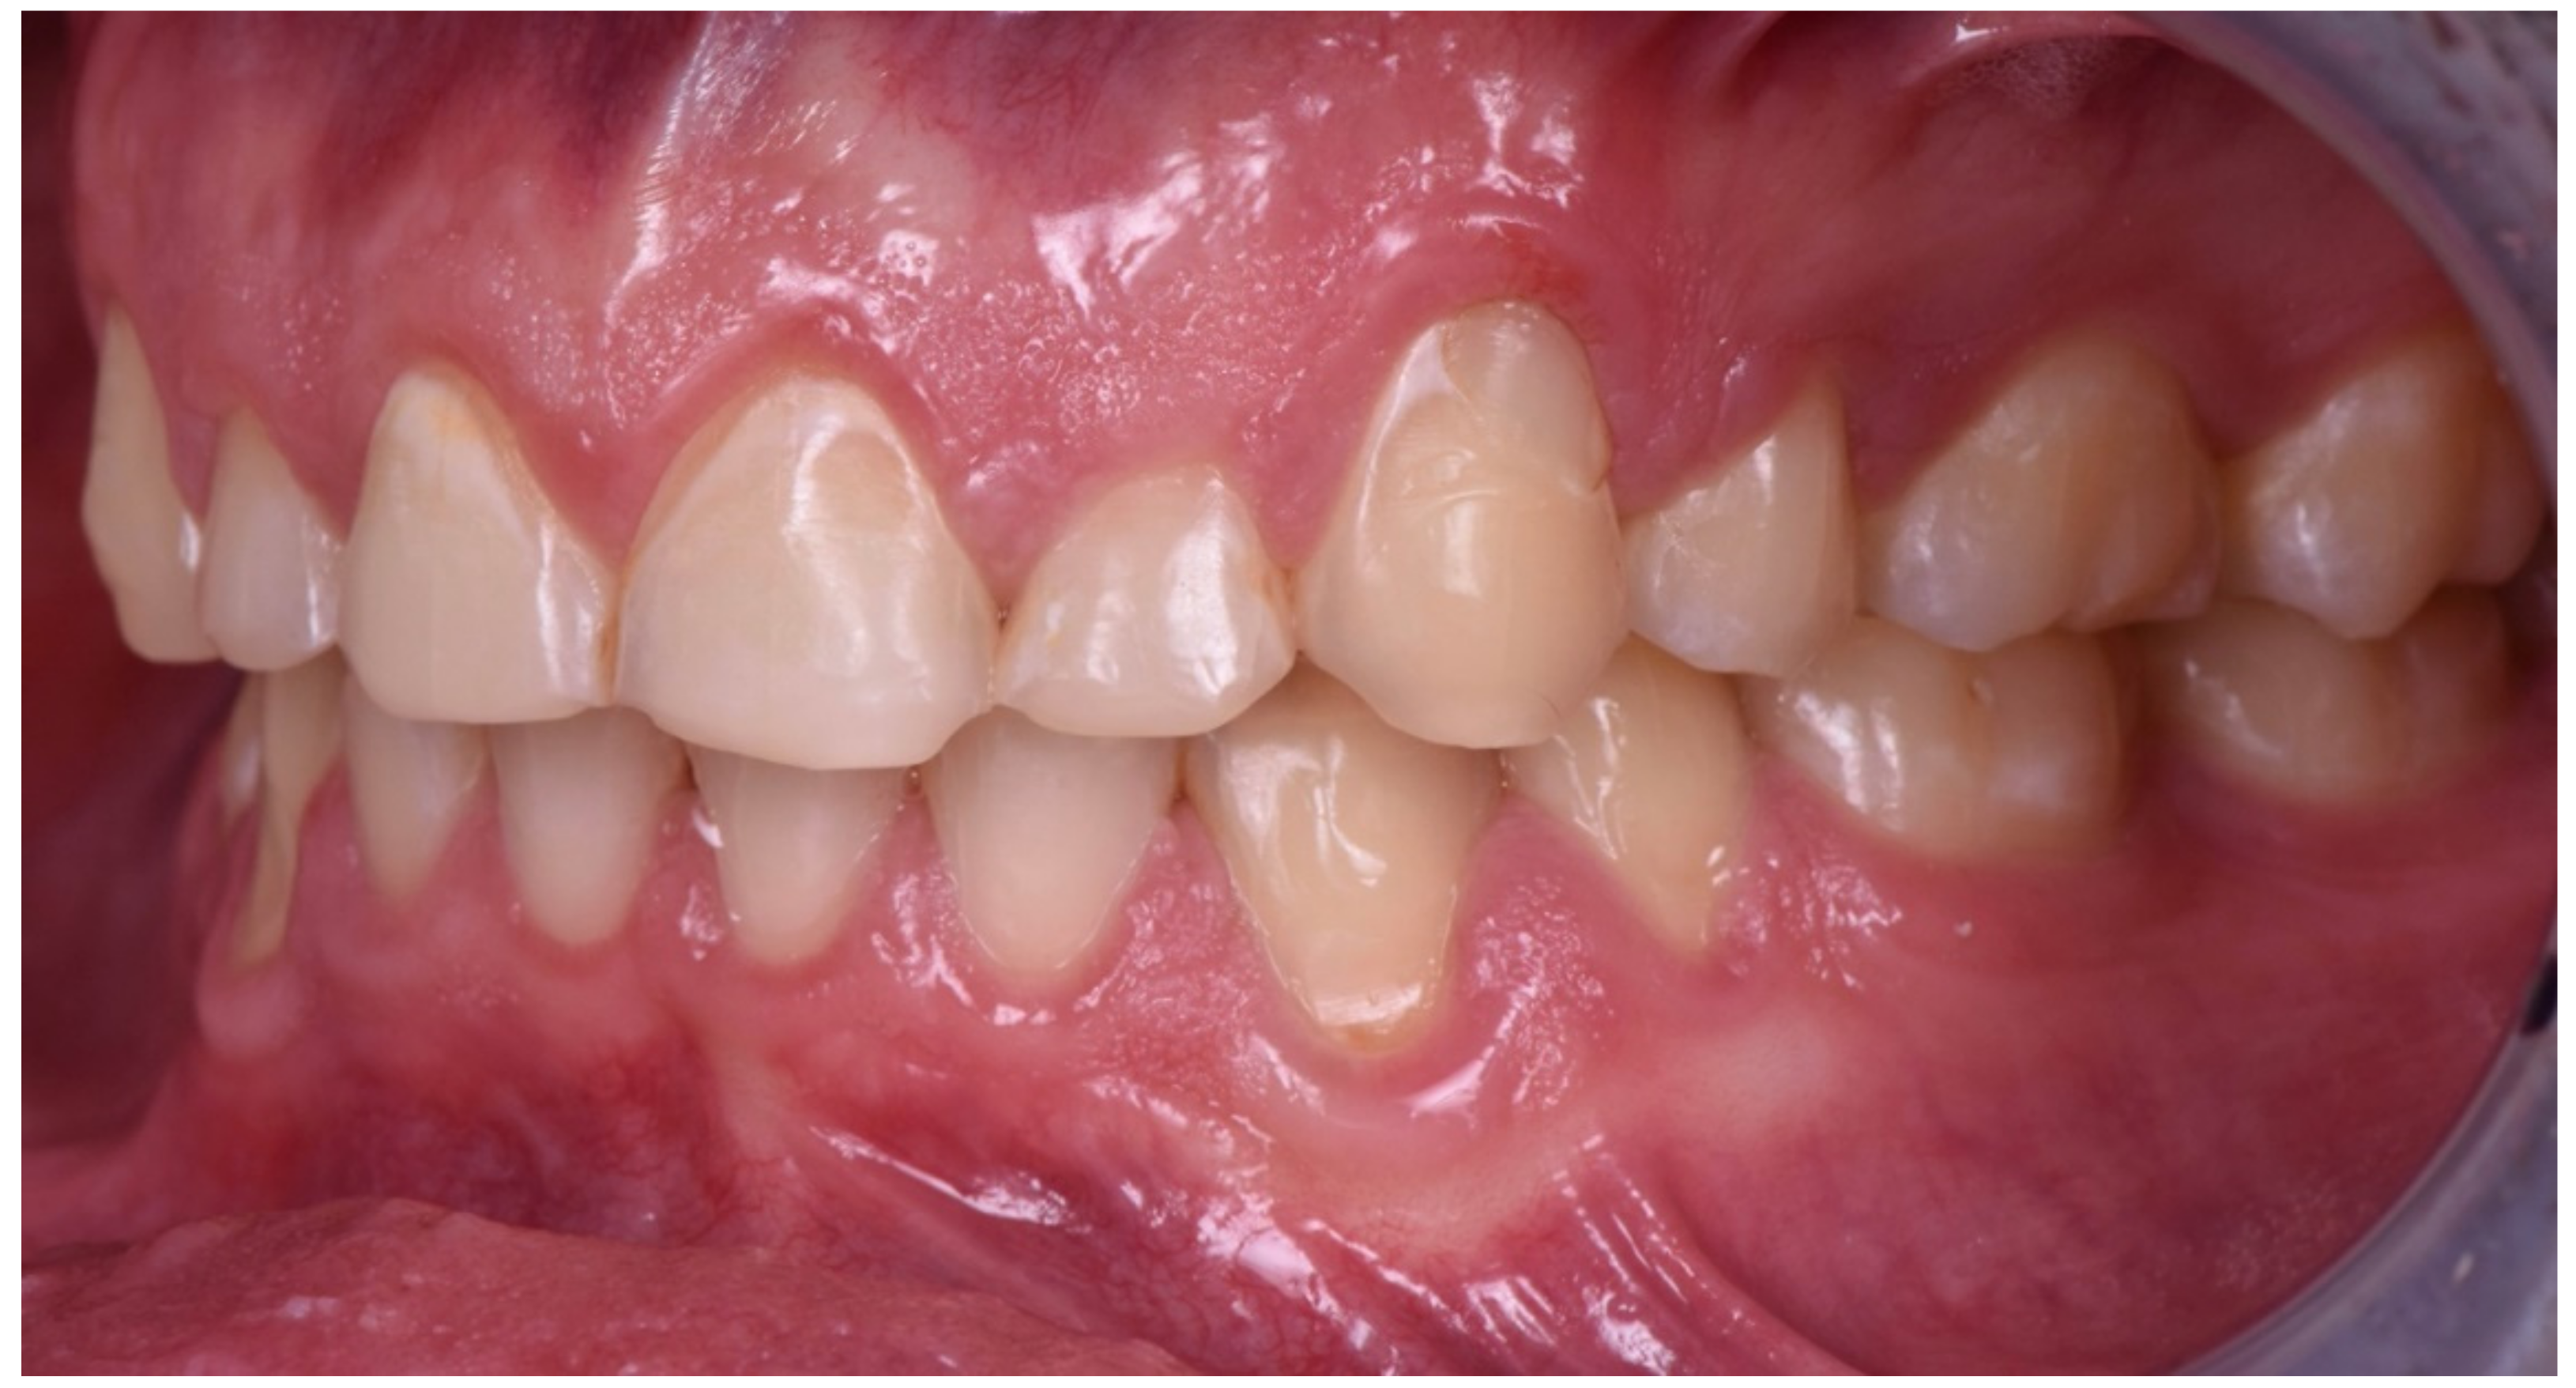

2. Clinical Report